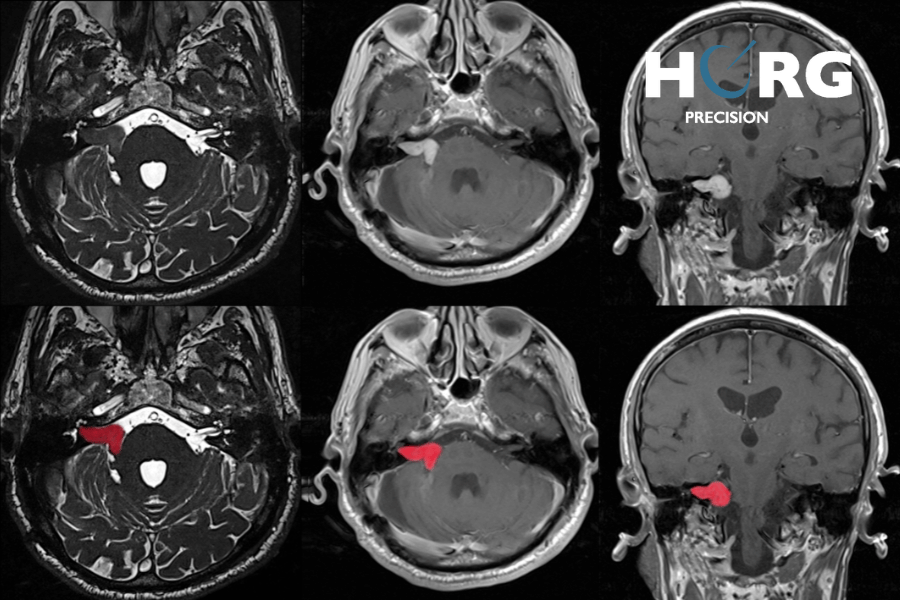

Enfin, l’IRM est l’examen d’imagerie médicale de référence pour diagnostiquer de façon formelle les schwannomes vestibulaires. Elle permet de visualiser les tumeurs, ainsi que leur localisation précise et leur impact sur les structures voisines.